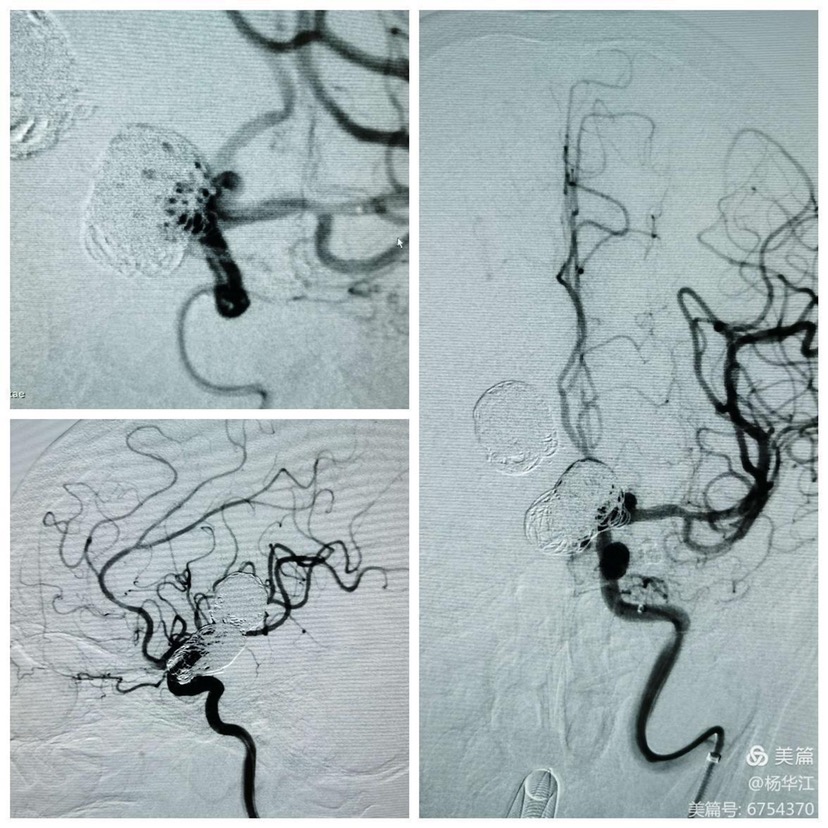

CTA及DSA显示:颈内动脉床突上段巨大动脉瘤(最大径25.6mm);基底动脉尖大动脉瘤(最大径20.3mm),瘤颈宽11mm,累及双侧大脑后动脉、小脑上动脉,右侧大脑后动脉自瘤体侧后方发出。

双侧股动脉穿刺,左侧椎动脉置入6F长鞘+5Fnavien,右侧椎动脉置入6F Enoy导管,选取第一个工作位,准备超选右侧大脑后动脉。

先echelon10微导管瘤内成襻技术超选入右侧大脑后动脉远端,拉直解襻微导管,交换phenom导管到右侧大脑后动脉远端,由于瘤颈超宽,导管再次疝入成襻才能超选至右侧大脑后动脉远端。

换第二个工作角度,prowlerplus微导管顺利超选至左侧大脑后动脉远端,echelon栓塞导管置于瘤腔内。

4.0x35pipeline经成襻的phenom导管缓慢送人右侧大脑后动脉远端,锚定,缓慢半释放至基底动脉中上段。

然后填圈至动脉瘤中、上部致密填塞,下部近分支处疏松填塞,同时释放左侧EP2支架,尾端紧贴pipeline侧方呈T形放置。最后稍推拉完全pipeline至基底动脉中下段。(这是本次手术有瑕疵的地方,尾端覆盖基底动脉稍长了一些,与我们测量计算误差有关)

术后即刻造影显示瘤体中上部已完全不显影,仅下部可见造影剂,基底动脉各分支显影良好。

术中先行后循环造影显示:动脉瘤几乎完全不显影,各分支显影良好。这个效果还是有些出乎我们的意料的好,大概率消除了迟发性出血这个隐患。

Pipeline结合弹簧圈处理左侧床突上段巨大动脉瘤

动脉瘤相对窄颈,射流比较明显。

填两枚大圈后,动脉瘤下半部分已经不显影,此时见动脉瘤上半部分射流明显,直冲瘤顶。

需要继续填圈阻断射流!

填圈至此,射流被阻断,瘤顶已不显影。

DynaCT双容积显示pipeline贴壁良好。